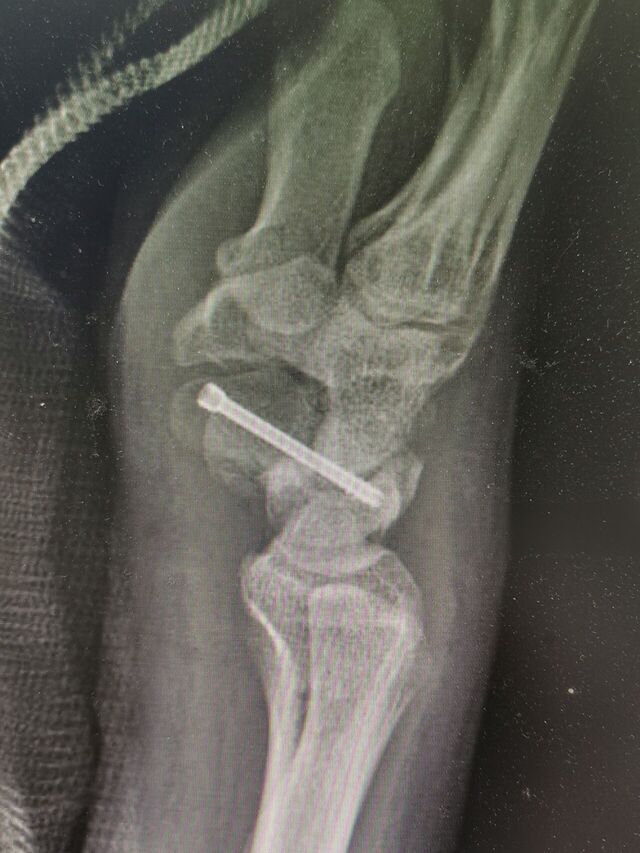

舟骨陈旧骨折,驼背畸形

术中失去对合参照

IMG_20240807_154525.jpg

IMG_20240807_154538.jpg

IMG_20240807_154625.jpg